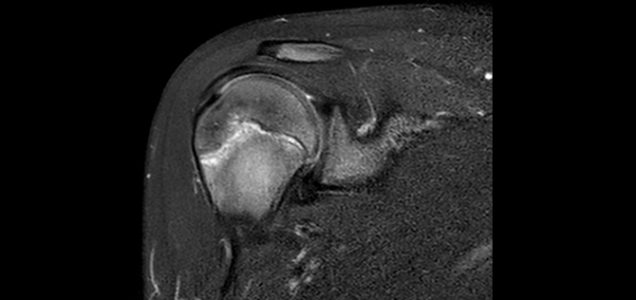

Young baseball players are prone to elbow and shoulder overuse injuries, especially pitchers. Little League Shoulder, most commonly seen in adolescent pitchers, is a stress injury of the growth plate of the upper arm bone (humerus). The growth plate is prone to this injury due to the accelerated growth at the proximal humeral growth plate. The diagnosis may be made on the basis of clinical findings with X-rays or, on some particular occasions, an MRI.